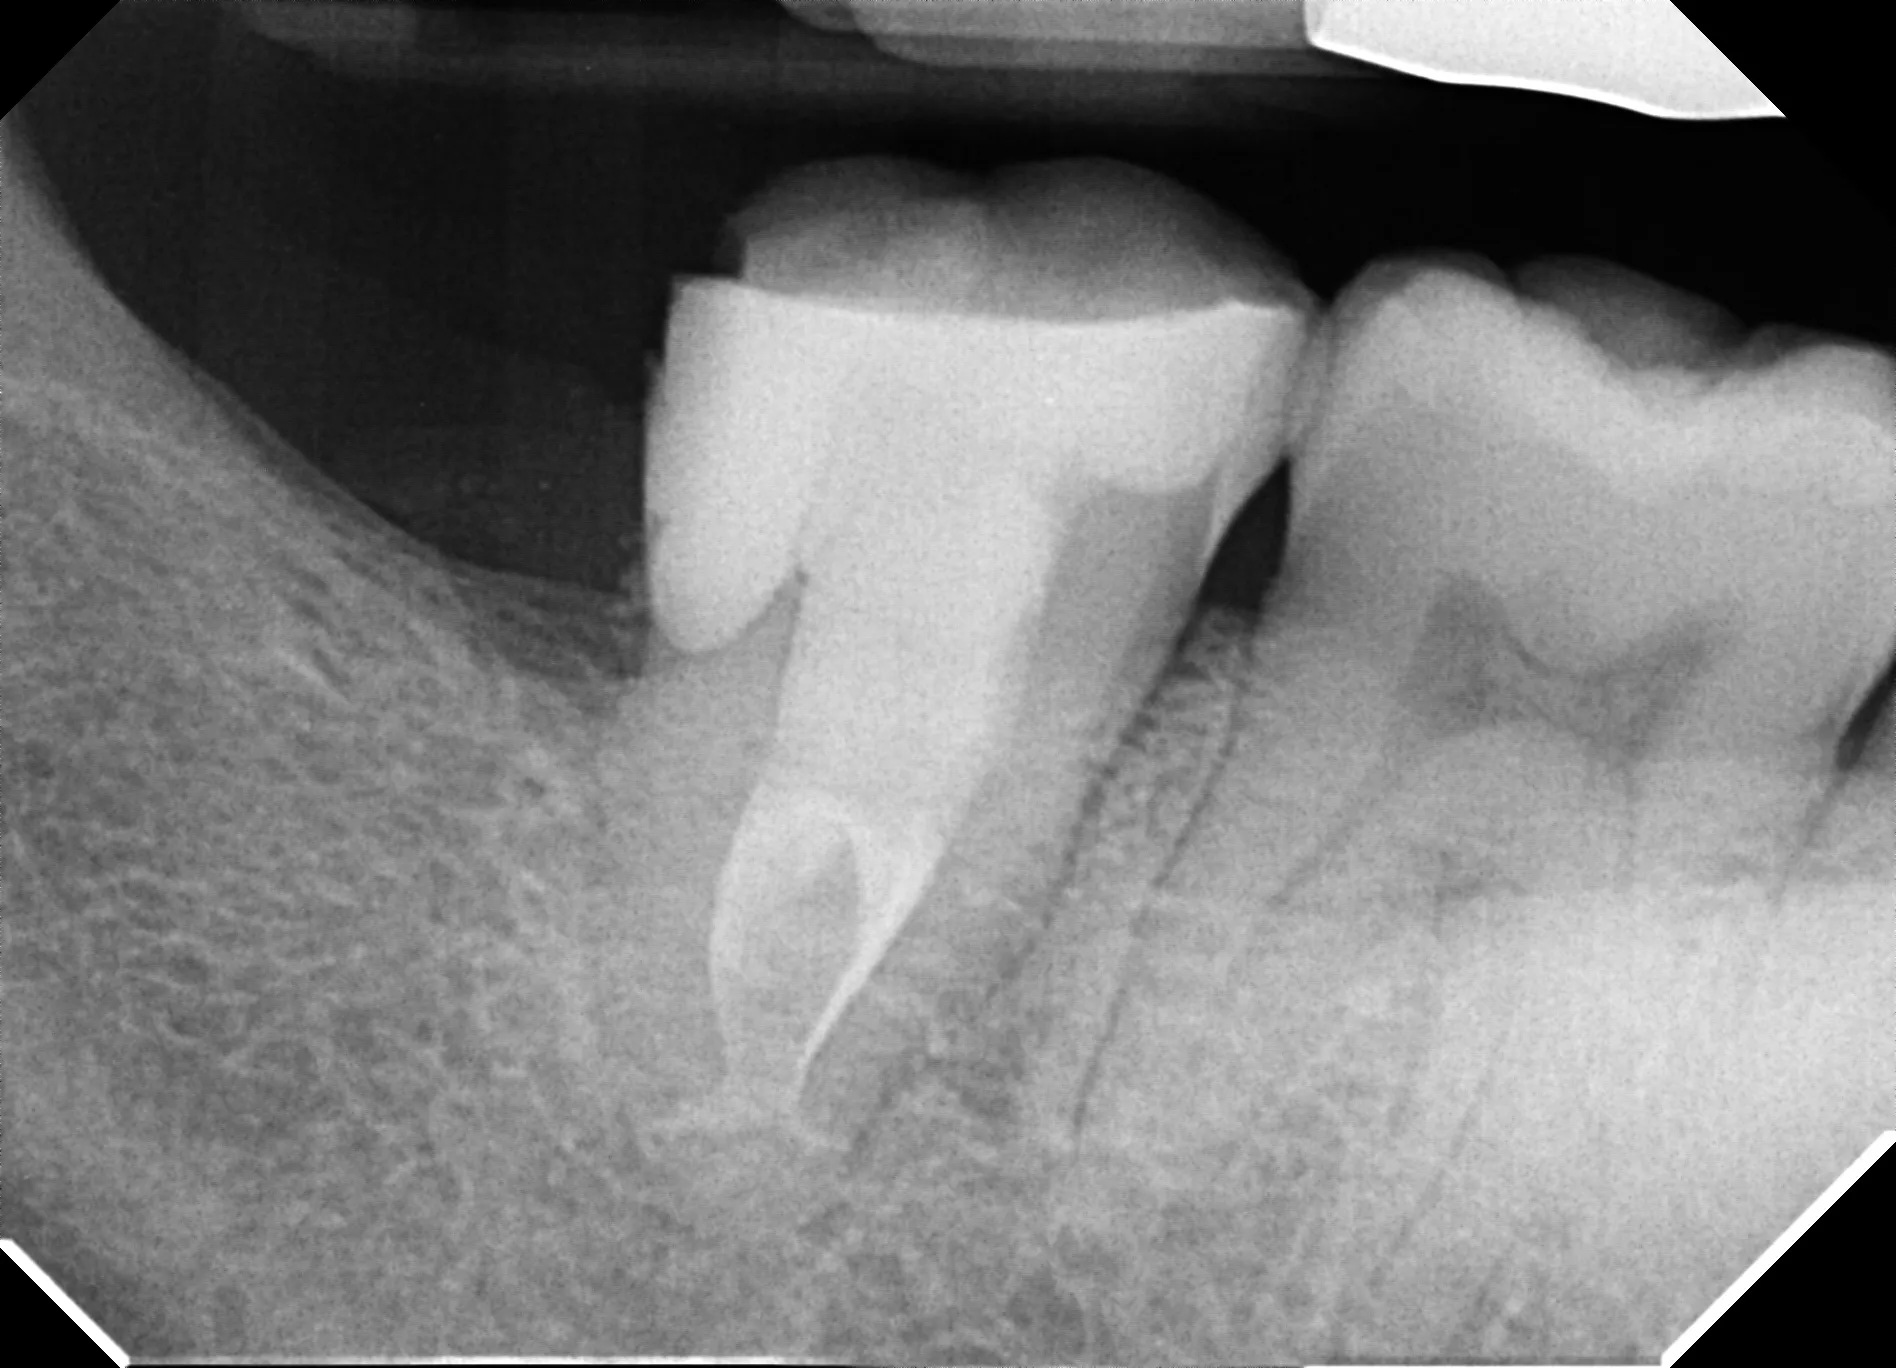

C-shaped canals occur in approximately 30-45% of mandibular second molars in certain populations, but they're rarely encountered by general dentists because the anatomical variation isn't visible on standard radiographs. This patient's CBCT revealed a Type I C-configuration—a continuous ribbon of pulp tissue connecting what would normally be separate mesial and distal canals.

This case demonstrates why anatomical knowledge distinguishes specialist practice from routine dentistry. The referring dentist suspected "something unusual" based on the radiograph and wisely referred before attempting treatment. Had standard techniques been applied, the result would likely have been incomplete debridement and persistent infection.

• Radiographs that show "merging" canals in mandibular molars suggest C-shaped anatomy

• Radiographs lie: Two-dimensional images cannot reveal three-dimensional ribbon-like anatomy. When something looks "weird," get CBCT before proceeding.